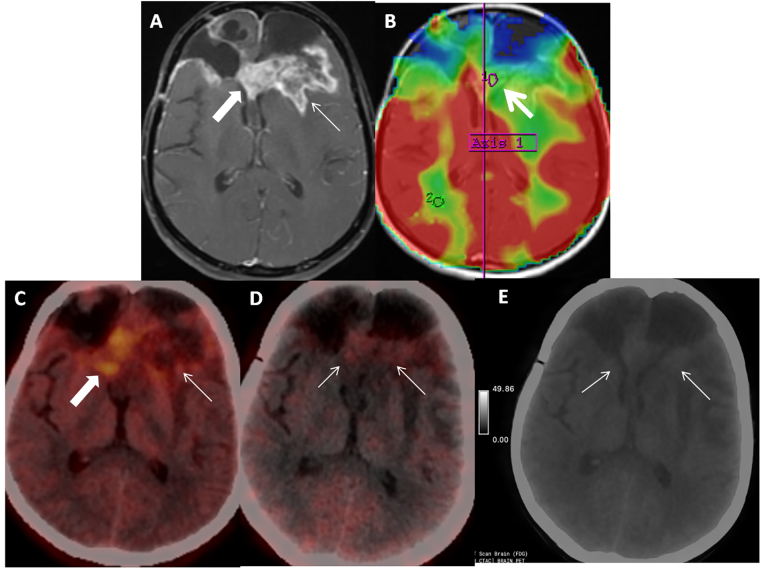

Fibroblast-activated protein (FAP) expression in glial cells is attributed to FAP-positive foci on tumor vessels and neoplastic cells. Preclinical and pilot studies have shown FAP expression in high-grade gliomas. We aimed at comparing PET imaging with FAP-inhibitor (FAPI-PET) with current standard, i.e., fluoro-ethyl tyrosine (FET) PET in post-treatment setting to differentiate recurrence and post-treatment changes. 6 patients with WHO Grade III and IV glioma who received standard treatment underwent Ga-68-FAPI-04 PET/CT (FAPI-PET/CT). Tracer uptake greater than background was considered positive. FET PET was performed and interpreted as per institutional standards, which formed the basis of treatment decision. There was concordance between FAPI expression and FET uptake in 5 patients suggestive of disease recurrence. There was no FAPI expression seen in 1 patient, in whom FET PET was suggestive of post-treatment changes. FAPI PET uptake correlated with amino acid expression to differentiate post treatment changes from recurrence in high-grade glial tumors; further validation with prospective study and histopathological confirmation is needed.

Abstract Image